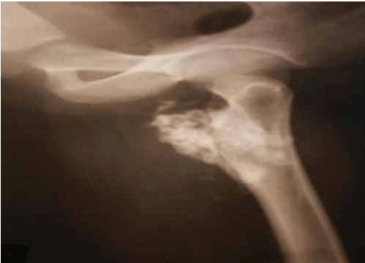

Here we report a 28 years old male present with pain in left hip and thigh due to proximal femoral Osteochondroma. Radiograph shows cauliflower-like mass originating from the left proximal femur. 3D CT scan of left thigh shows compression anterior displacement of femoral vessels near the bifurcation. This patient was treated with surgical en-bloc resection and histopathology was diagnostic of Osteochondroma.

Osteochondroma in the antero-medial aspect of subtrochanteric region of the left femur with origin abutting the lesser trochanter with a large cartilaginous cap causing compression anterior displacement of femoral vessels near the bifurcation.

Pre op X-Ray

Preop X-Ray